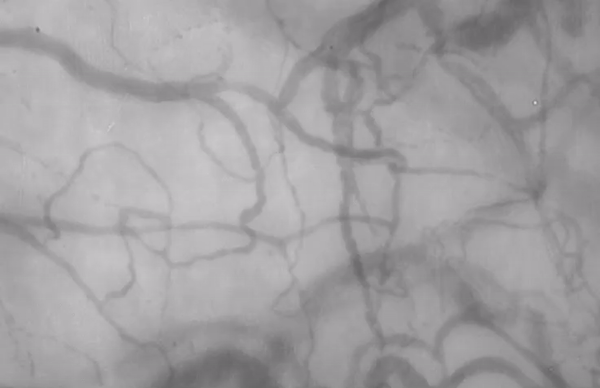

The GlycoCheck™ system measures PBR, vessel density and microvascular red blood cell filling to create a single overall health score to quantify the differences between a healthy and unhealthy circulatory system.

Unhealthy Microcirculation - Low Score 0.25 out of 10

Healthy Microcirculation - Average Score 4.67 out of 10

Unhealthy Microcirculation - Low Microvascular Score

0.6 out of 10 (Month 0)

Healthy Microcirculation - Average Microvascular Score

3.9 out of 10 (Month 4)